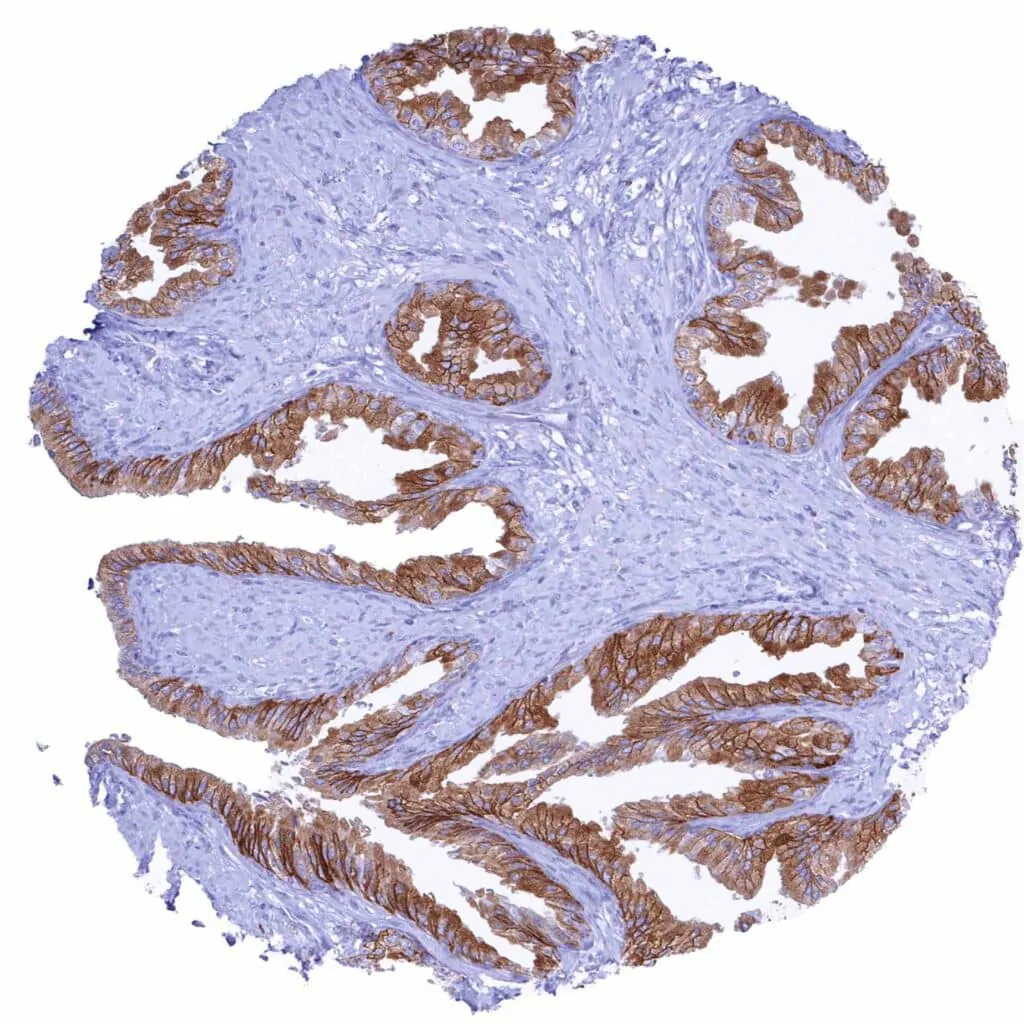

Prostate – Strong membranous CD38 staining of most epithelial cells. Staining is weaker or absent in basal cells